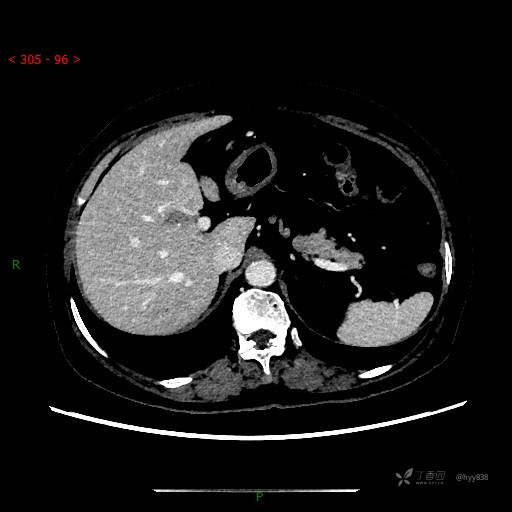

上腹部CT平扫